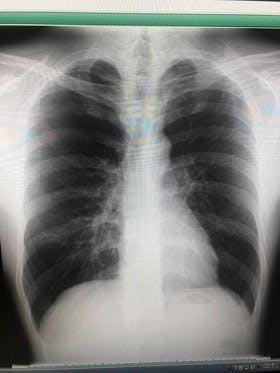

こんにちは!昨日3回目の診察へ行きました!前回の投稿でも書いたように痛みや息苦しさが無くなったのでよくなってるんじゃないかなあと思いながら行きました。結果はちょっとだけ肺が膨らんでいました。痛みが無いのと肺が膨らんでいるということでおそらく穴はふさがっているだろうという見解です。ただ、塞がった...